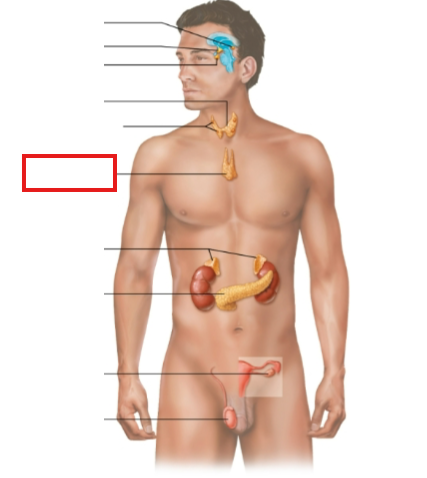

What structure is highlighted?

pineal gland

hypothalamus

pituitary gland

thyroid gland

parathyroid glands

thymus

adrenal glands

pancreas

ovary (female)

testes (male)